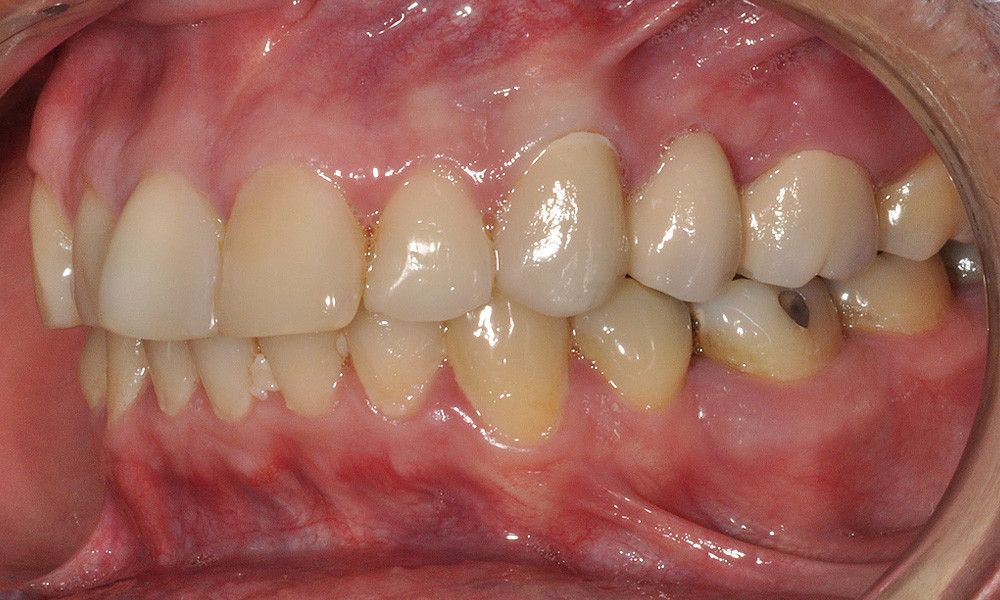

Reporte del Caso: Paciente sexo masculino, 36 años, con diagnóstico de esquizofrenia y trastorno bipolar en tratamiento. Consulta por el recambio de dos prótesis fijas plurales (PFP) de reemplazo de dientes 4 y 13 con pilares en piezas 3, 5, 12 y 14 mediante rehabilitaciones unitarias de los dientes pilares y reemplazo mediante implantes en zonas edéntulas.

El estudio imagenológico evidencia una pérdida ósea severa en altitud y grosor, situación que complejiza la colocación de un implante. Se analizan alternativas de tratamiento y se opta por una vestibuloplastía mediante autoinjerto conectivo de mucosa palatina que se reposiciona sobre la zona del defecto óseo. Además se realiza retratamiento de ambas PFP, ahora en zirconia, por motivos estéticos y oclusales. Se realizan controles posteriores para evaluar la respuesta gingival a la vestibuloplastía.